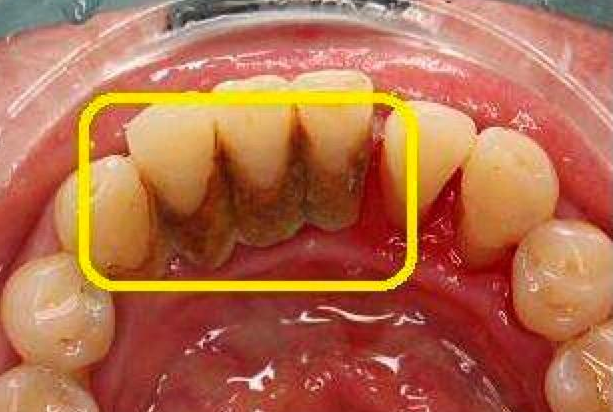

牙結石是牙齒表面硬化形成的沉積物,主要由食物殘渣、細菌及其代謝產物組成。隨著時間的推移,這些沉積物會逐漸鈣化,形成難以通過日常刷牙清除的硬塊。牙結石不僅影響美觀,更重要的是它能導致牙齦炎、牙周病等口腔疾病,對口腔健康構成嚴重威脅。